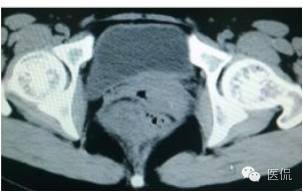

增强延迟期(CT值106HU)